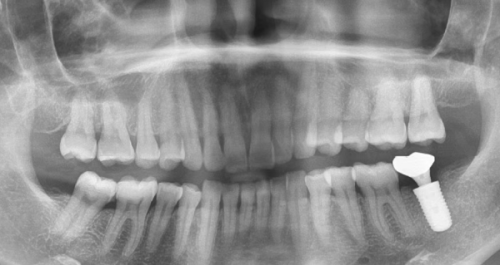

当麻醉生效后,医生会在种植体上方小心翼翼地切开牙龈组织。这一步就像是打开一扇隐藏的门,目的是暴露埋藏在骨组织内的种植体顶部。种植体在之前的一期手术中已经被植入到骨组织里,现在需要把它的顶部露出来,为后续的操作做准备。医生的手法非常精细,就像一位技艺高超的工匠,确保切开的位置和范围恰到好处,尽量减少对周围组织的损伤。

接下来就是基台安装环节。医生会先旋出封闭螺丝,然后仔细清理种植体内部的螺纹。这就好比打扫房子,把里面的“灰尘”清理干净,为新成员的到来做好准备。之后,医生会根据你的牙龈厚度选择合适的愈合基台,并将其旋入固定。愈合基台就像是一座桥梁,连接着种植体和未来要安装的牙冠。合适的基台能够确保后续牙冠的安装更加稳固和舒适,就像给房子打好了坚实的地基。

基台安装完成后,医生会对周围的牙龈进行缝合或塑形。这一步的目的是确保未来牙冠修复时有良好的穿龈轮廓。想象一下,穿龈轮廓就像是牙冠的“出场通道”,一个理想的通道能够让牙冠更加自然地融入口腔环境。在部分情况下,医生可能还会放置临时牙冠来辅助牙龈成型。临时牙冠就像是一个“小助手”,帮助牙龈更好地适应和塑形,为更终牙冠的安装创造更好的条件。